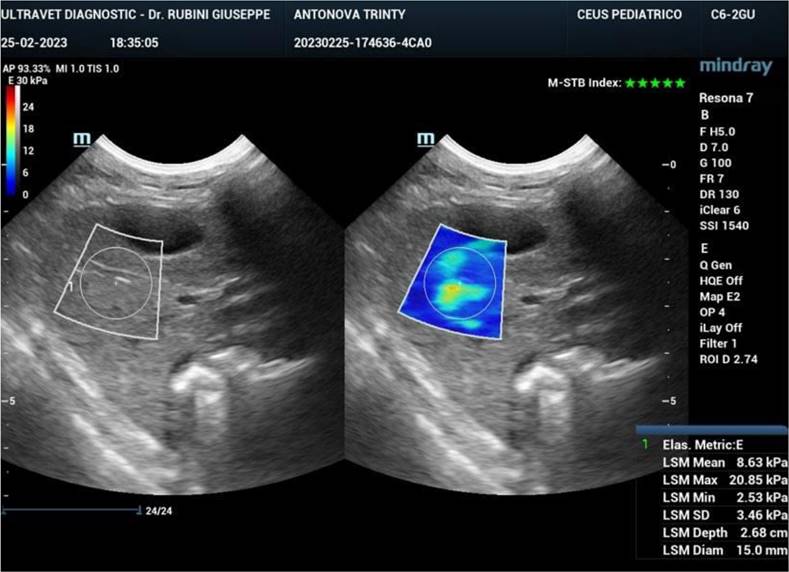

Ultrasound elastography (also known as sonoelastography) was used to support the diagnosis and management of diffuse liver disease. Elastography can identify early-stage and advanced liver fibrosis and thus is a major application in clinical liver care. In addition, elastographic characterization of focal liver lesions and evaluation of clinically significant portal hypertension can potentially be clinically useful and are areas of active clinical research. Currently, the accepted liver fibrosis staging reference standard is the histopathologic evaluation of non-focal liver biopsy specimens. However, liver biopsy has some limitations: 1) liver biopsy is invasive, 2) liver biopsy is costly, and 3) inter-observer variability limits the clinical interpretability of liver biopsy samples. To this end, 34 dogs treated with exosomes were followed also by sonoelastography to evaluate the presence and reduction of fibrosis after 180 days from the first injection of exosomes. As reported in Figure 7, fibrotic tissue with alteration of blood flow (highlighted in the circle) is visible before the treatment. Figure 8 shows that the fibrotic event is no more present and the portal vein blood flow has recovered after 180 days from the first injection of exosomes.

Figure 7

Sonoelastography of the canine liver before injection of autologous exosomes. Fibrotic tissue and altered portal vein blood flow are shown.

Nanotheranostics Image